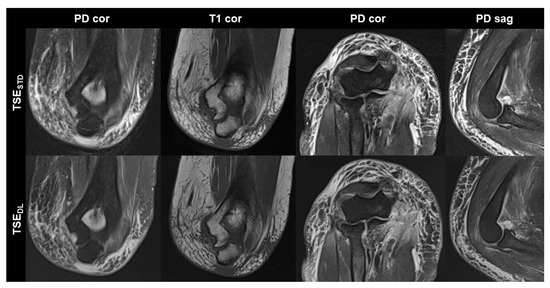

TSEDL was successfully performed in each of the 17 included participants (mean age 43 ± 16 (20–70), years, eight men). Seven exams were performed at 1.5 T and 10 exams at 3 T. TSEDL enabled a scan time reduction by more than 35% at 1.5 T (TSEDL 8:19 min vs. TSESTD 13:06 min) and by more than 55% at 3 T (TSEDL 6:48 min vs. TSESTD 15:15 min). Image examples with comparisons of TSESTD and TSEDL are displayed in Figure 1, Figure 2, Figure 3 and Figure 4.

Figure 2. Non-contrast elbow MRI acquired at 3 T in a 70-year-old male patient with the institution’s standard turbo spin echo (TSE) sequences (TSESTD, upper row) and deep learning-reconstructed TSE sequences (TSEDL, lower row). In this example the standard and DL-reconstructed images show very similar image quality. In the TSEDL images, all anatomic details are well depicted, showing that the reduced acquisition time did not lead to a loss in detail. Additionally, edge sharpness in the coronal T1-weighted images (T1 cor) is slightly increased in the TSEDL image.